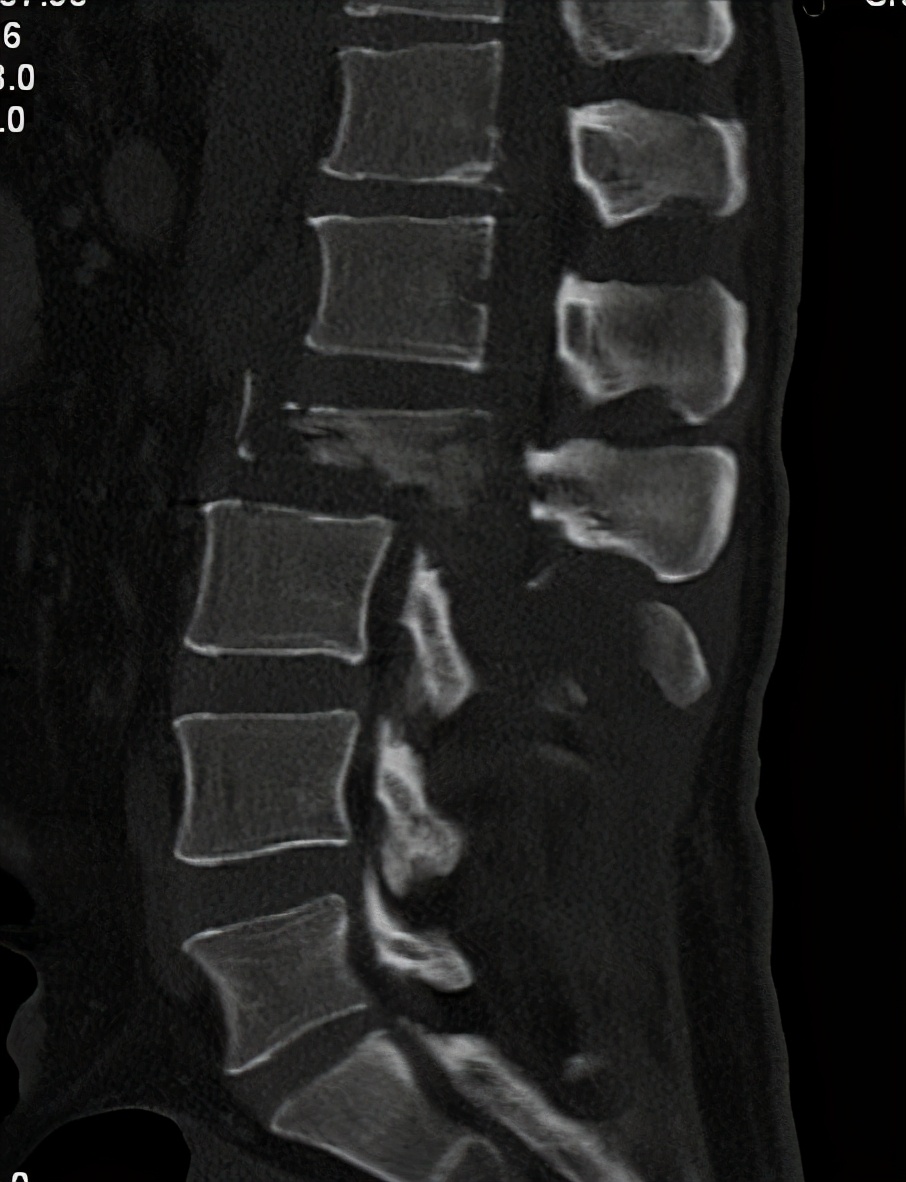

诊断为:1、 腰2椎体爆裂性骨折伴截瘫

腰椎CT